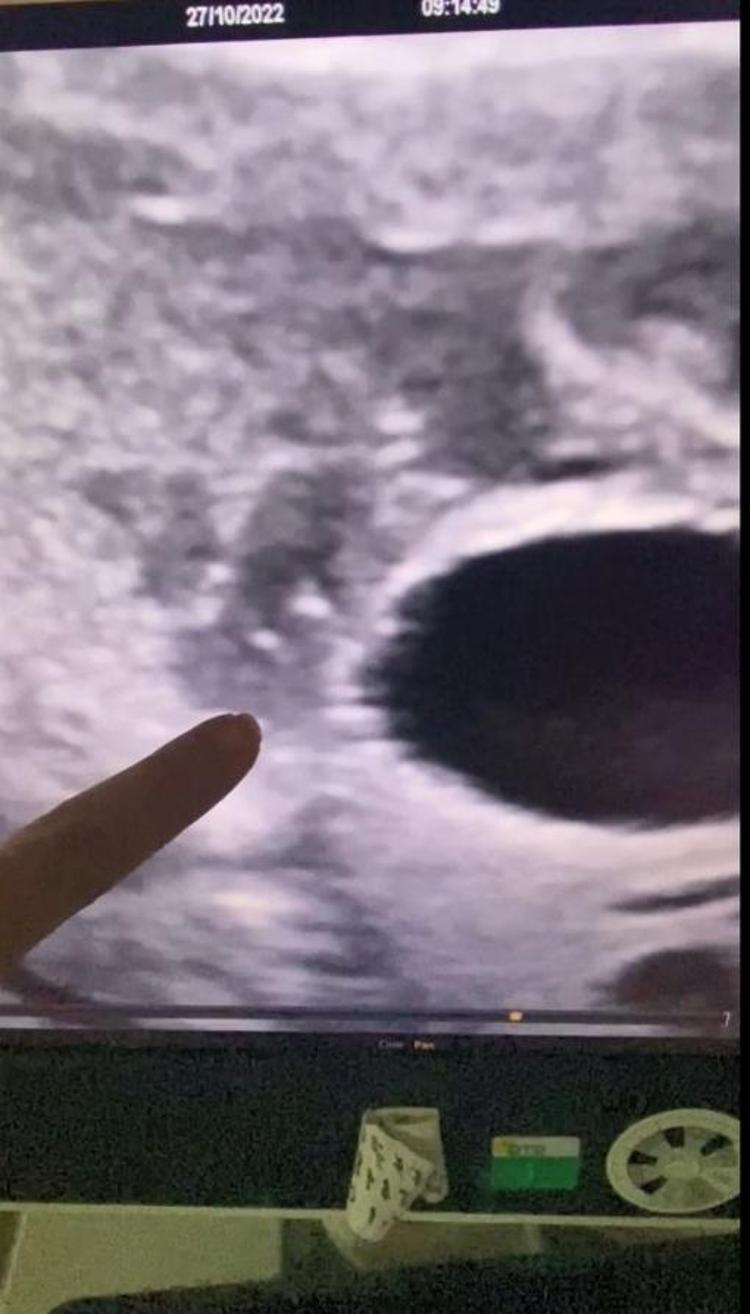

Anne karnında idrar çıkış yolunda darlık tespit edilen bebeğe stent takıldı

Yapılan operasyonla stent takılan bebeğin idrarını yapması sağlandı.

Uygulanan işlemin oldukça hassas olduğunu ifade eden Dr. Birsen Konukçu Palta, “Vesicoamniyotik Stent uygulaması ile bebeğin idrar kesesine takılan bir kanül ile idrarını yapması sağlanır.